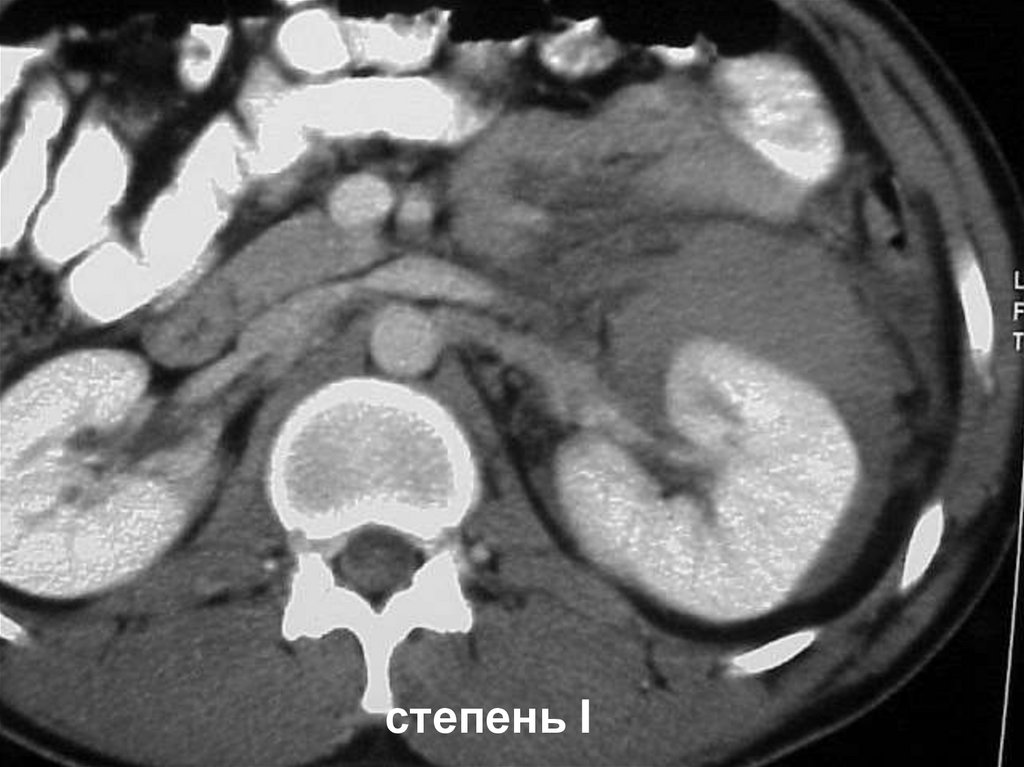

степень I

Разрыв почки <1 см., параренальная гематома

Разрыв почки >1 см., параренальная гематома

степень III

степень V